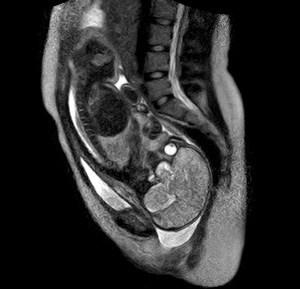

Hochinteressant! Nur stimmt m. E. die Bildunterschrift zum MRT-Bild nicht: "MRT-Bild von der Geburt: Der Kopf des Kindes liegt tief im kleinen Becken eingangs des Geburtskanals. Die Augen "blicken" auf die Wirbelsäule der Mutter". Also ich würde sagen, dass dieses Bild vor der Geburt gemacht wurde, denn der Kopf ist eindeutig noch oben - zumindest hängt da die Wirbelsäule dran ...;-)) Dann die Lunge. Das unten ist "tief im kleinen Becken" ist jedenfalls nicht das Kind. Würde ich selbst als absoluter Laie behaupten. Wie siehst Du das? LG Schlaflos

das is definitiv der kopf, der da im kleinen becken der mutter liegt.:) dieses weisse gebilde ganz unten ist die fruchtblase, die graue masse der kopf bzw. dsa gehirn des kindes und das auge vom zwerg sind ja mehr als deutlich zu sehen, das guggt sich grad das steissbein von mami an. von uns aus gesehn links ist die wirbelsäuke von zwerg,das graue haifischflossen ähnliche gebilde ist zwergens lunge, der schwarze fleck der bauch und danach kommt das kindliche becken.